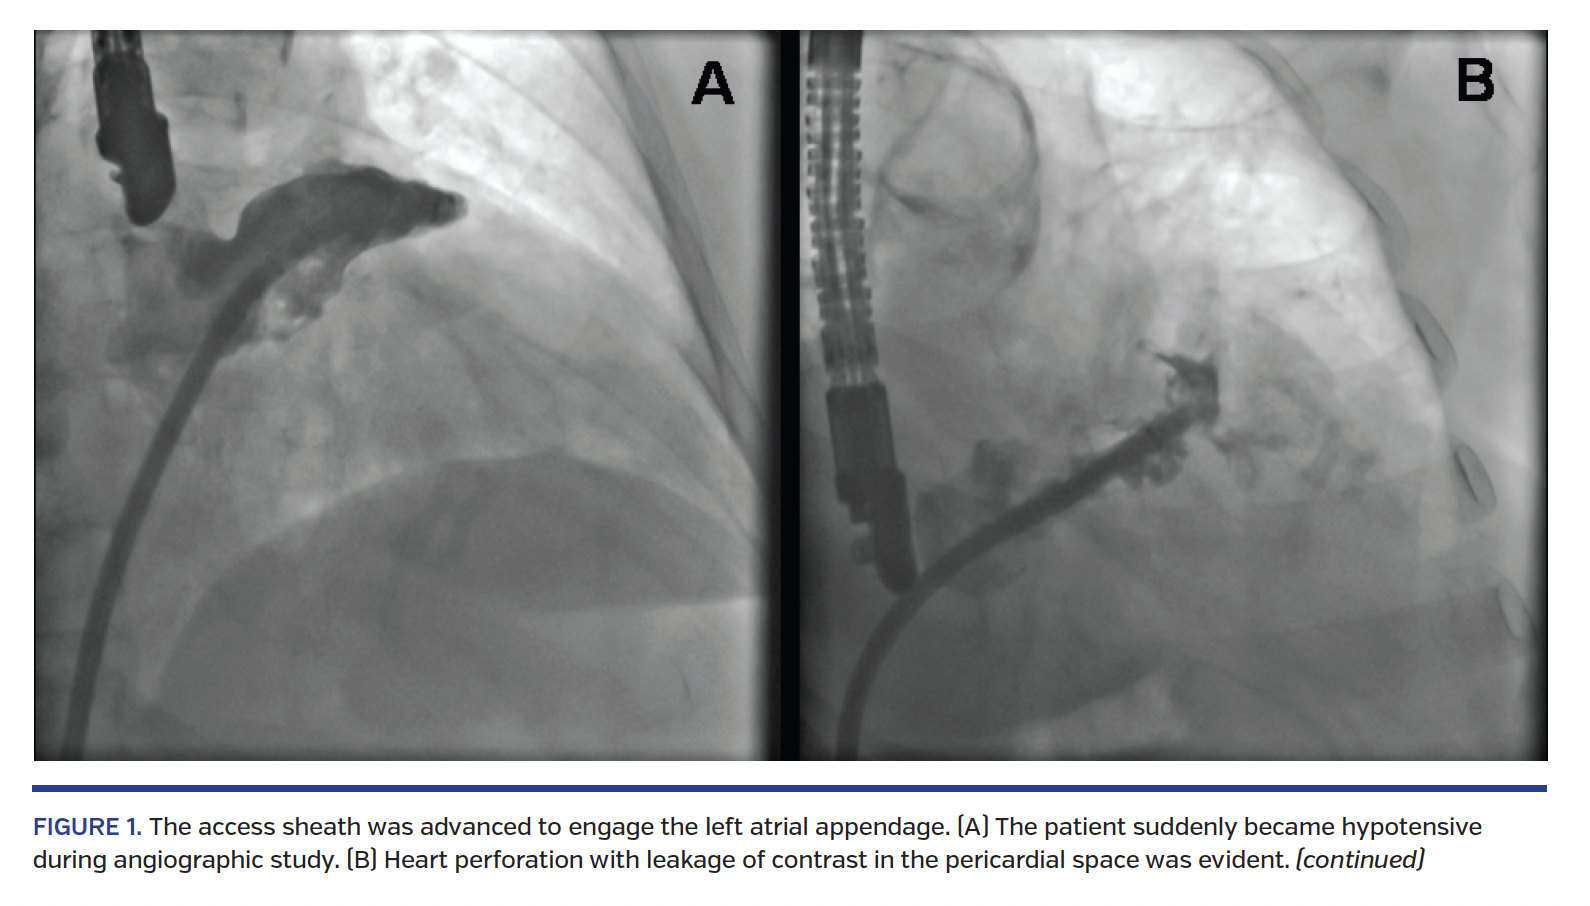

After right venous femoral access (14 Fr) and transseptal puncture, we advanced the access sheath on an extra-stiff guidewire to engage the LAA. During angiographic study (Figure 1A), the patient suddenly became hypotensive. Heart perforation with leakage of contrast in the pericardial space was evident (Figure 1B) and TEE confirmed cardiac tamponade.

We proceeded as follows: (1) rapid release of 30 mm Watchman closure device in the LAA (Figure 1C); (2) pericardial drainage and aspiration of 1100 mL of blood; (3) autotransfusion with direct reinfusion of 950 mL of blood through right venous femoral access; and (4) infusion of 50 mg intravenous protamine sulfate.

After 50 minutes, we achieved hemodynamic stabilization; angiography (Figure 1D) and TEE showed complete drainage of blood from the pericardial space without contrast leakage and good position of the closure device. The patient was transferred awake to the intensive care unit to continue monitoring.